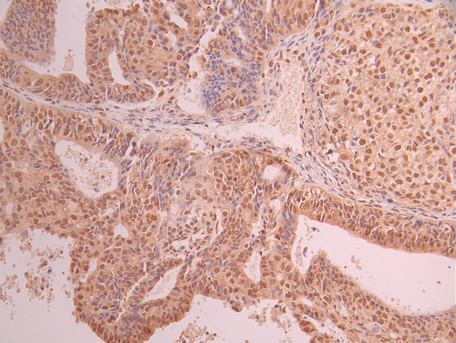

IHC image of CSB-RA948463A0HU diluted at 1:100 and staining in paraffin-embedded human ovarian cancer performed on a Leica BondTM system. After dewaxing and hydration, antigen retrieval was mediated by high pressure in a citrate buffer (pH 6.0). Section was blocked with 10% normal goat serum 30min at RT. Then primary antibody (1% BSA) was incubated at 4°C overnight. The primary is detected by a Goat anti-rabbit polymer IgG labeled by HRP and visualized using 0.05% DAB.